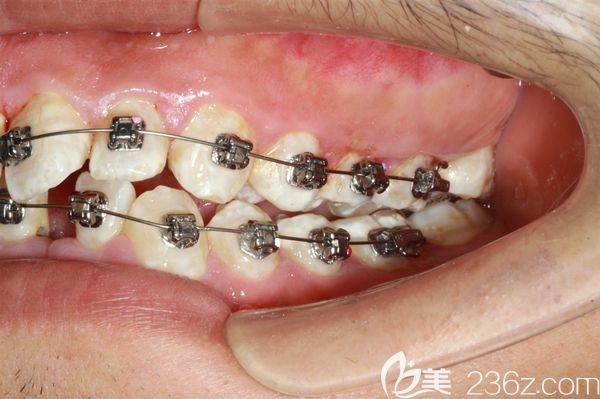

男朋友牙齒太難看,分享和他去廣州陽(yáng)光樹口腔做門牙齙牙深覆蓋矯正后臉型變化圖 b1557 G0 V0

男朋友牙齒太難看了,給大家分享下他在廣州陽(yáng)光樹口腔做門牙齙牙矯正+牙齒排列不齊的深覆蓋臉型變化圖,快來看看他現(xiàn)在變成什么樣了。